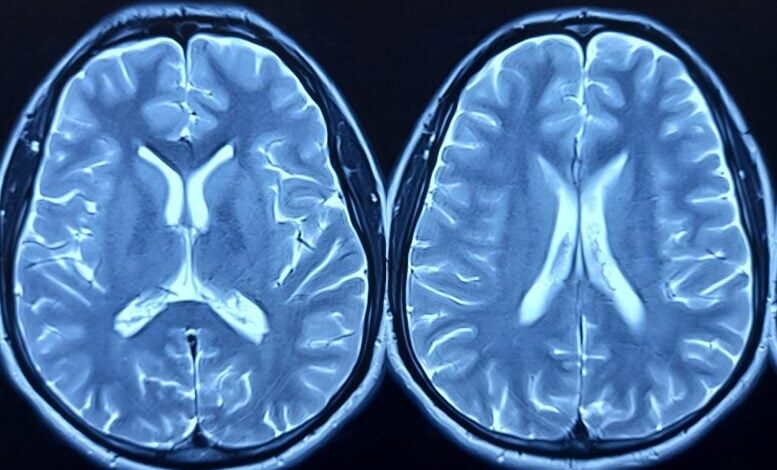

Případová studie Penn zjistila, že rozhraní mozek-počítač ukazuje, že lék má pouze krátkodobé nebo neúplné účinky na související mozkovou aktivitu u pacienta s obezitou, což zdůrazňuje potřebu dalšího výzkumu. Vzácný pohled na mozkovou aktivitu pacienta s obezitou a ztrátou kontroly nad jídlem, který užíval tirzepatid (prodáno (…)